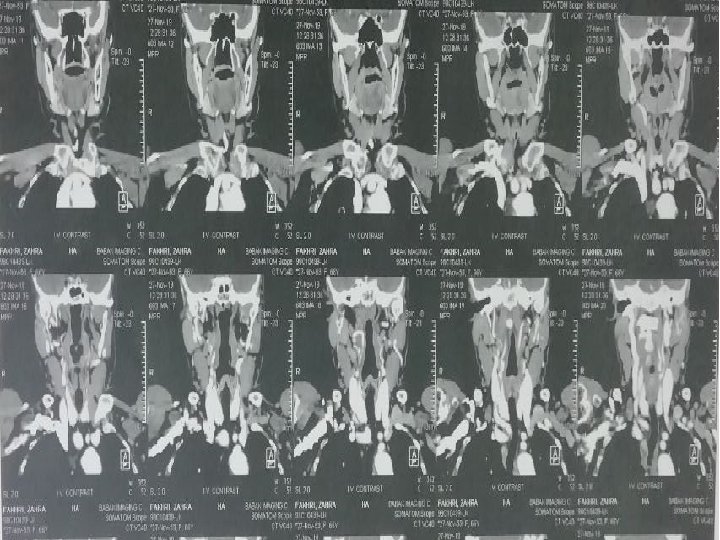

CT Scan axial of neck with and without IV Contrast 98/6/9